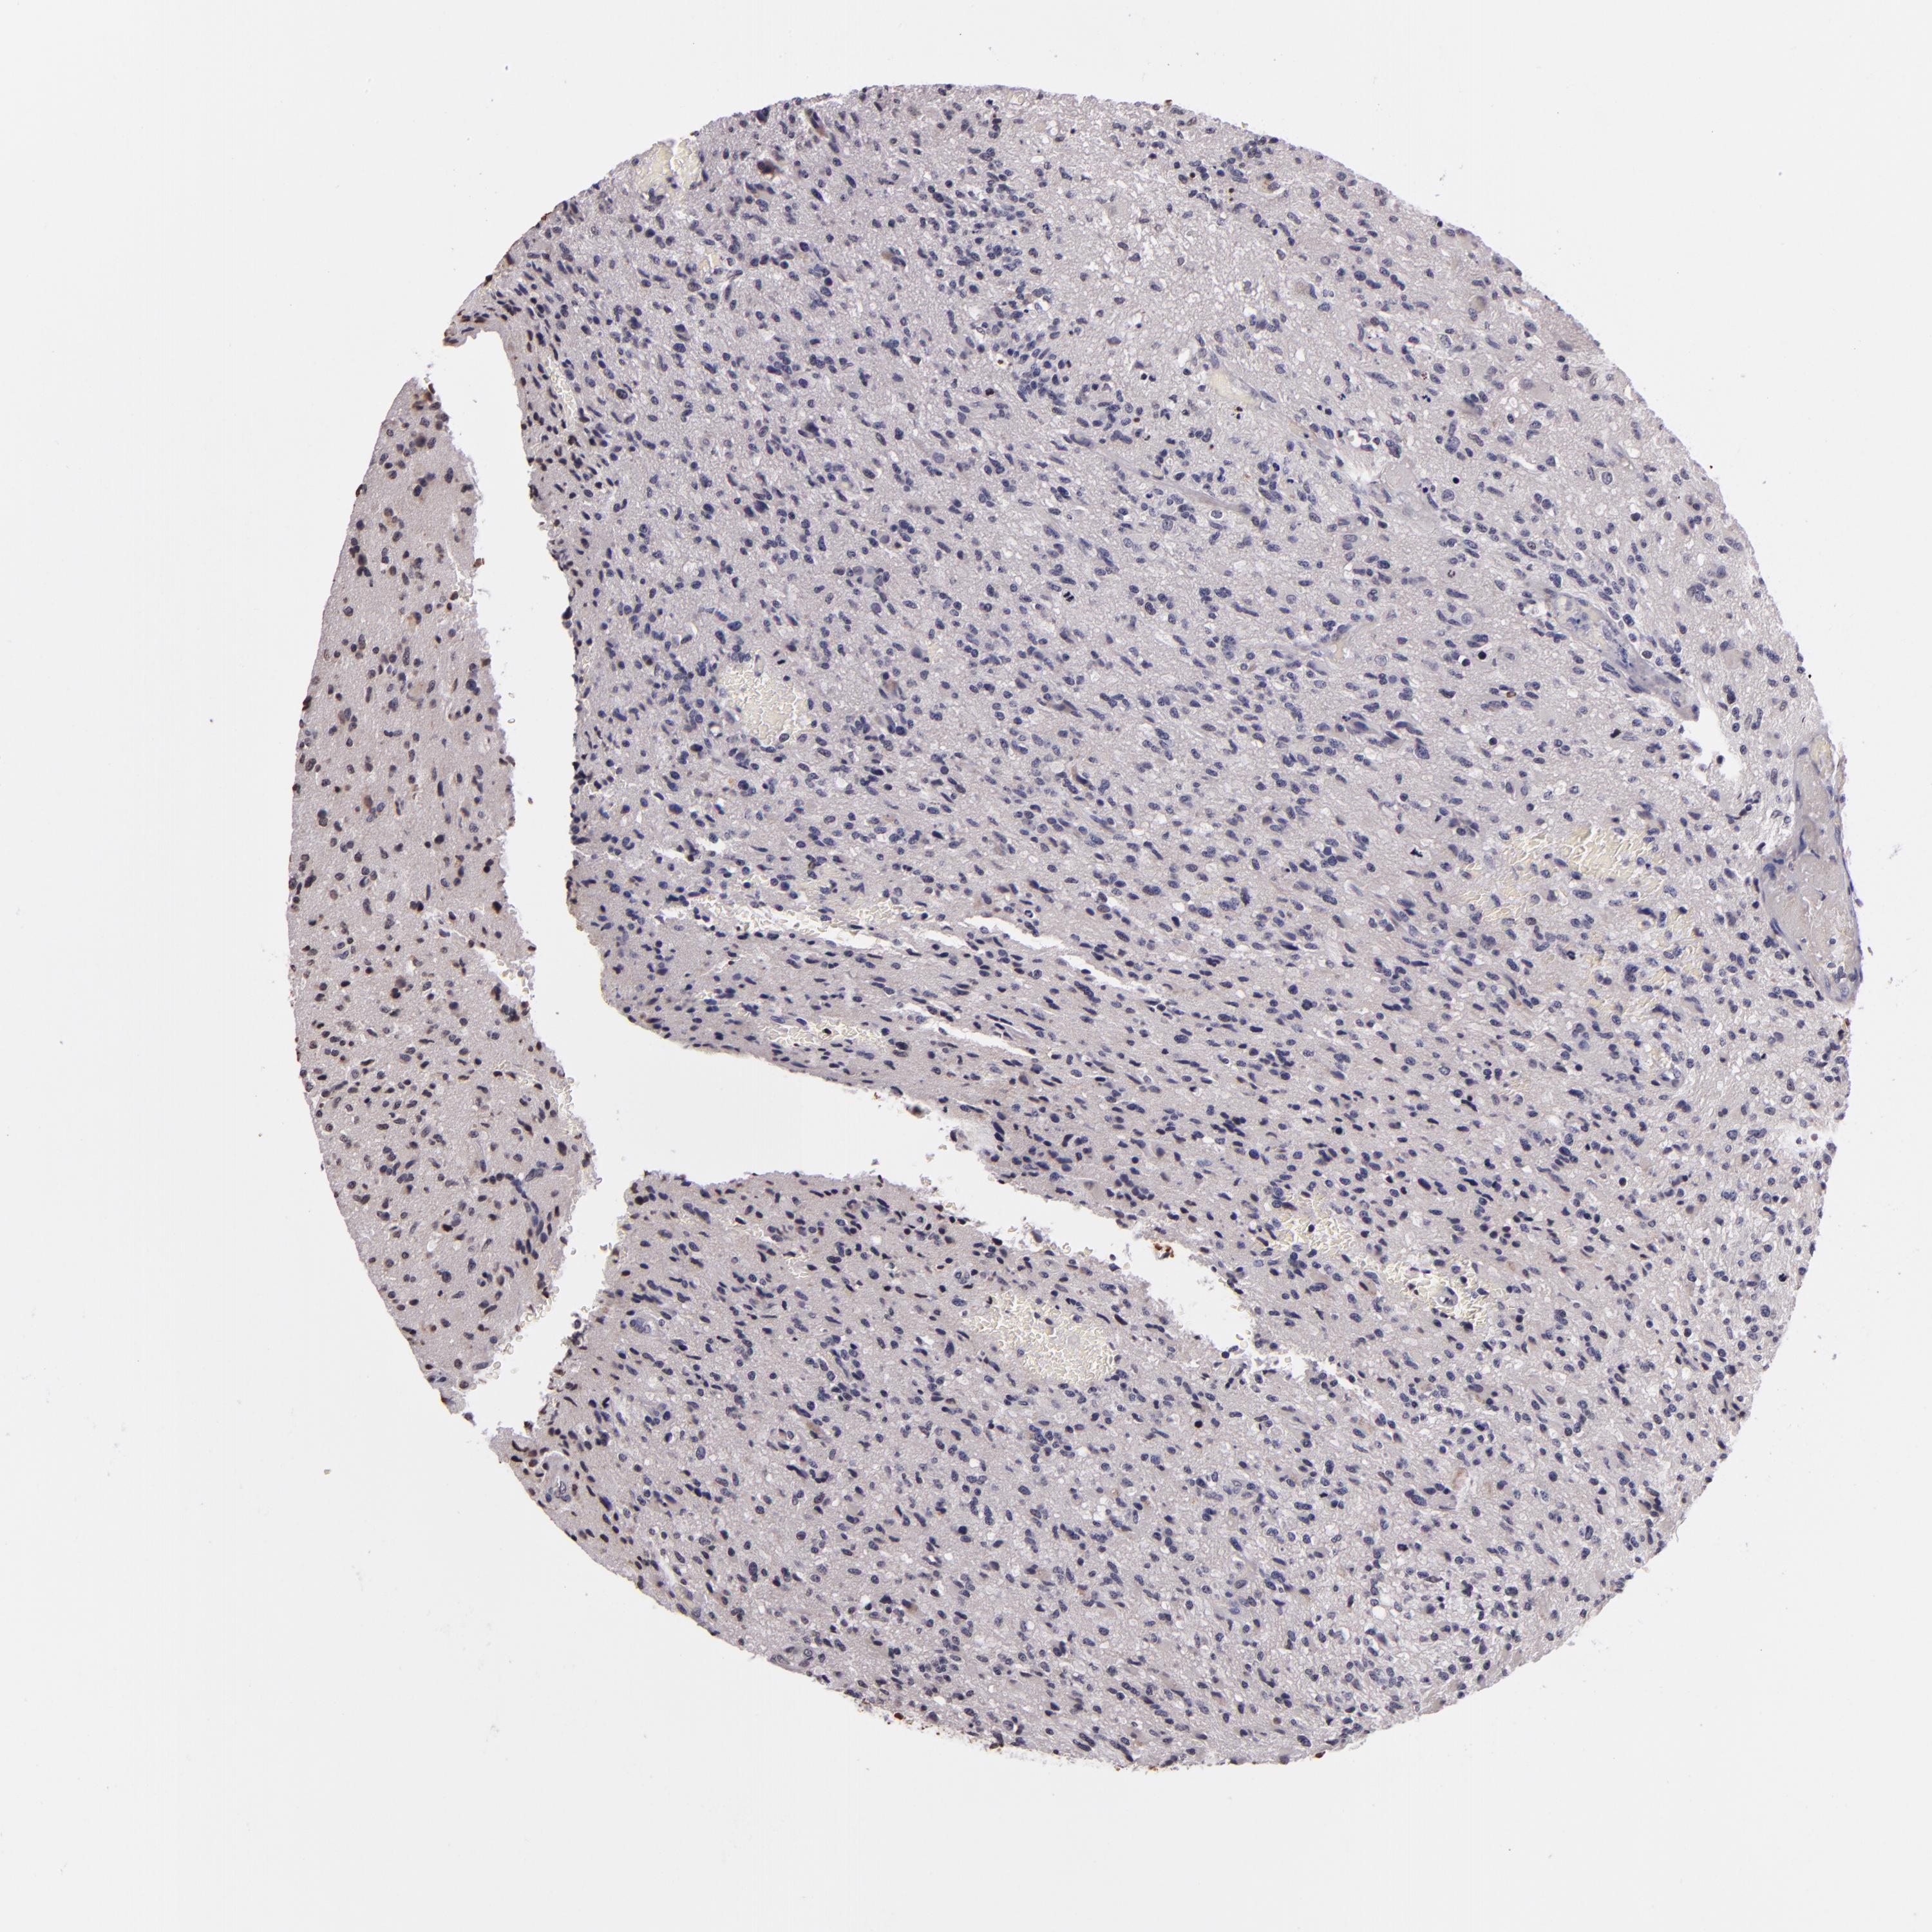

GLIOMA - Protein expressioni

A mouse-over function shows sample information and annotation data. Click on an image to view it in a full screen mode. Samples can be filtered based on level of antibody staining by selecting one or several of the following categories: high, medium, low and not detected. The assay and annotation is described here.

Note that samples used for immunohistochemistry by the Human Protein Atlas do not correspond to samples in the TCGA dataset.

Antibody stainingi

Antibody staining in the annotated cell types in the current human tissue is reported as not detected, low, medium, or high, based on conventional immunohistochemistry profiling in selected tissues. This score is based on the combination of the staining intensity and fraction of stained cells.

Each image is clickable and will lead to virtual microscopy that enables deeper exploration of all samples and also displays staining intensity scores, fraction scores and subcellular localization as well as patient and tissue information for each sample.

Antibody CAB002008

Antibody CAB002009

Staining

High

Medium

Low

Not detected

Intensity

Strong

Moderate

Weak

Negative

Quantity

>75%

75%-25%

<25%

None

Location

Nuclear

Cytoplasmic/membranous

Cytoplasmic/membranous,nuclear

Glioma, malignant, High grade

Glioma, malignant, Low grade